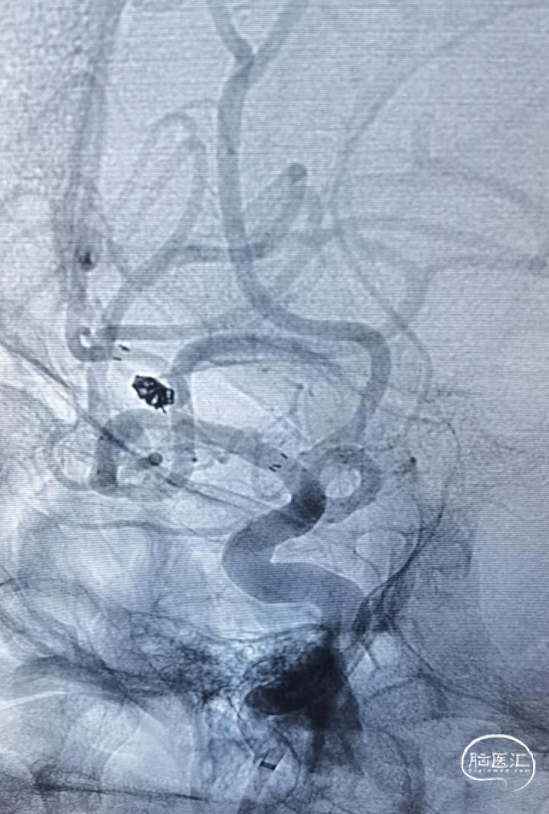

术中全身肝素化,6F DA导引导管到达颈内动脉C1段远端,根据3D图像选取工作角度造影充分暴露载瘤动脉、瘤颈、动脉瘤长径。

使用SL-10 微导管在Synchro 微导丝引导下分别进入载瘤动脉及动脉瘤腔内。

采取半释放法于上干释放3*21mm Altas支架1枚,同时于动脉瘤内填塞弹簧圈至致密。

最后全释放支架,序贯撤出微导管,造影可见支架打开完全、贴壁完美,载瘤动脉角度变化小,管腔通畅,动脉瘤Raymond 1级栓塞。